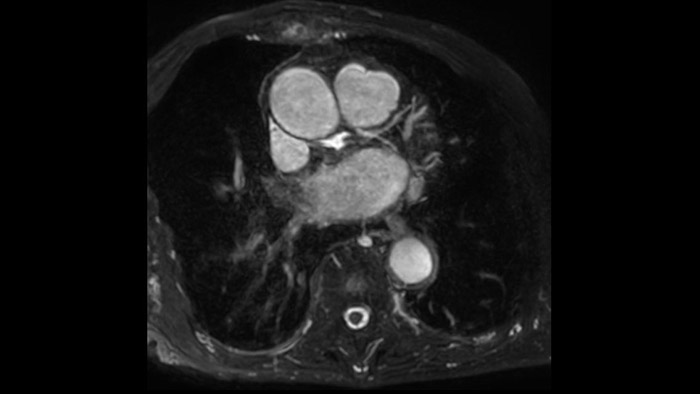

IntelliSpace Portal MR Caas5,6 4D Flow post-processing solution enables generation of 3D volume reconstructions, to visualise and evaluate blood flow in cardiovascular structures, including heart valves, chambers, and vessels, based on cardiovascular MR 4D Flow imaging.

Diagnostic and prognostic utility of cardiac MR is increasing. Assess the anatomy and function of the heart using cine acquisitions, acquire information about perfusion and viability of the cardiac tissue, visualise potential edema with black blood sequence, access and even quantify tissue characterisation with CardiacQuant.